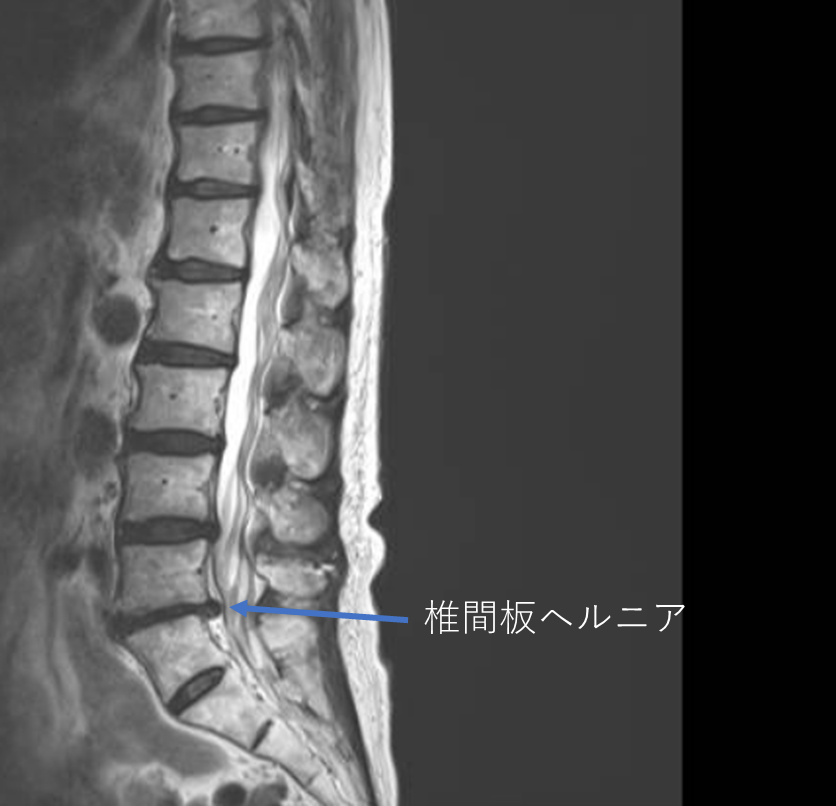

画像及び所見について

- L5/s-椎間板ヘルニア

- L1/2,2/3,3/4,4/5,5/s-椎間板変性症

以上の事が画像上認められます。

・L5/s-椎間板ヘルニアを認め、主症状の原因の可能性が高い

・L3/4,4/5-椎間板変性症を認め、予防的な意味合い